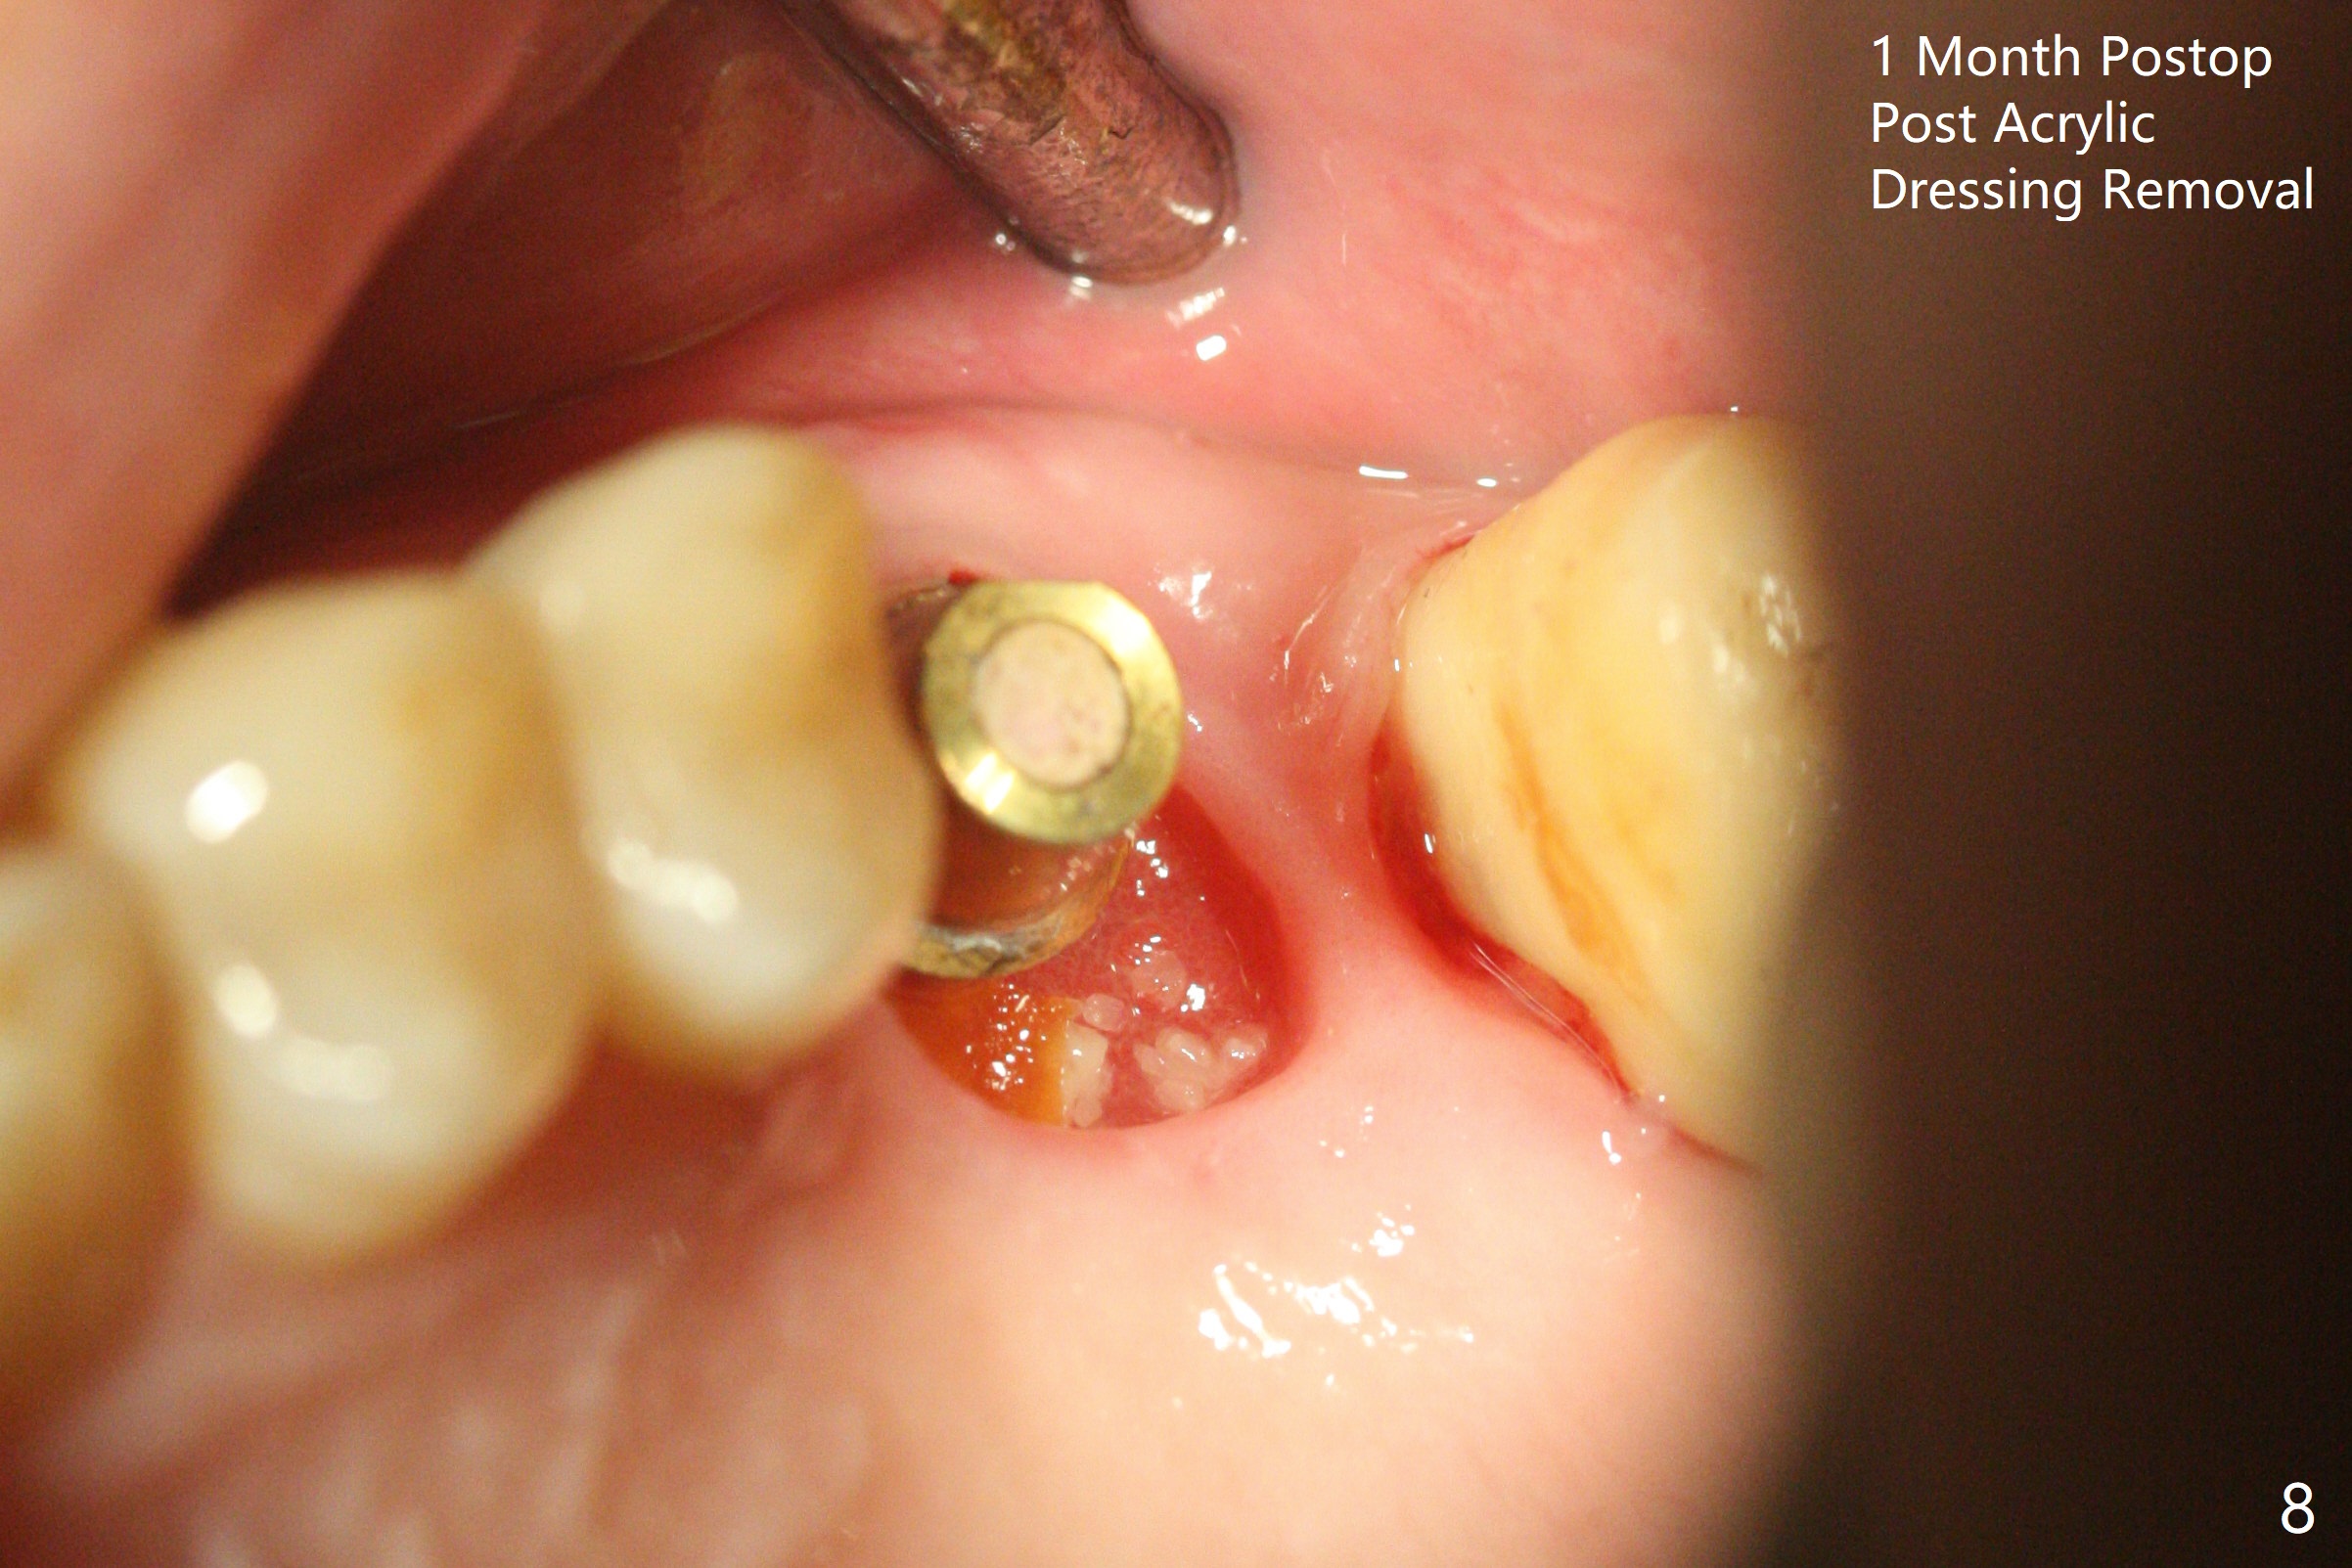

72岁男14号牙腭侧根尖接近上颌窦(图一,二:P),牙齿拔除后,根尖对刮治敏感,冲洗后,开始导板钻洞,圆钻穿透窦底,放置粘性骨粉和报废植体提升(图三:箭头)。放置小张PRF和骨粉(图四:箭头),植入正式植体,基台和骨粉(图五:*),最后覆盖PRF(图六),为了防止骨粉从邻牙牙龈沟(>)丢失,覆盖树脂敷料。基台和前后邻牙使树脂敷料术后一周巍然不动(图七:A)。术后一个月撤除树脂敷料,牙槽窝已经愈合(图八)。再过两周牙槽窝上皮好像进一步成熟(图九),然后塞入一个龈线,制备临时牙冠。